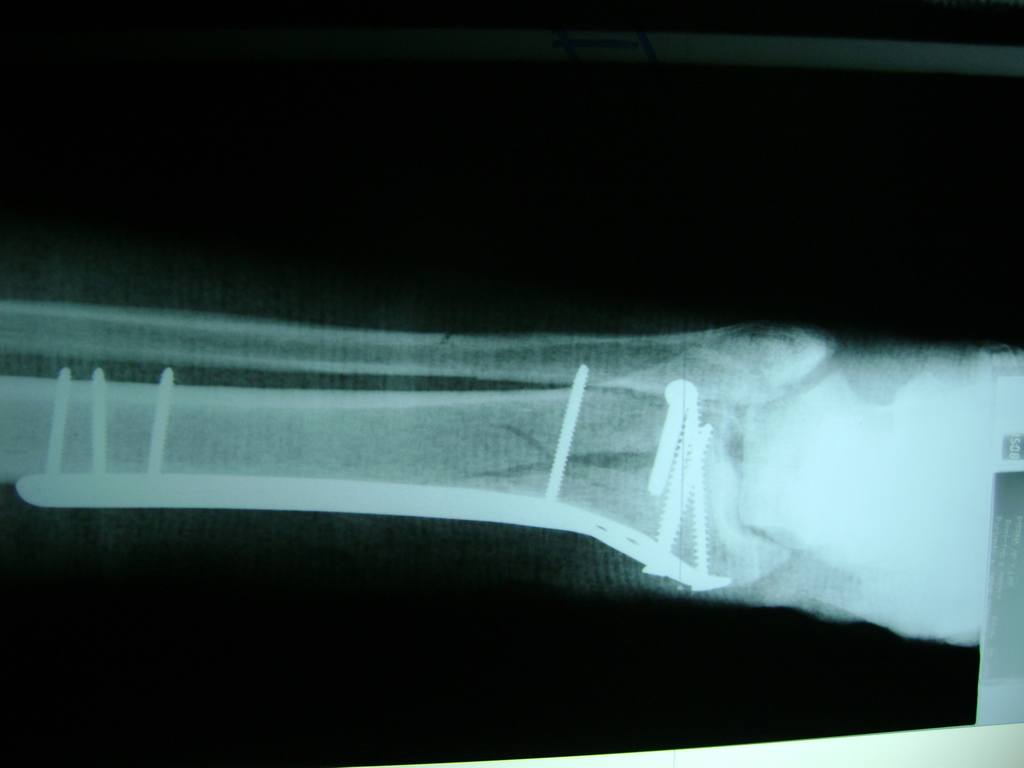

Cirugías de Hombros - Perone y Tibia

Aunque cada uno de estos huesos puede fracturarse por separado, normalmente la rotura es una lesión que se produce de forma conjunta

La mayor parte de las roturas implican a la parte proximal del hueso (parte del hueso próximo a la rodilla) o a la parte distal (parte del hueso cerca del tobillo).

Debido a la fina cobertura de piel que recubre la tibia y el peroné, las fracturas generalmente son abiertas, es decir, el hueso roto rasga la piel, atravesándola. Las fracturas de tibia y peroné generalmente se producen por un fuerte impacto o torsión.